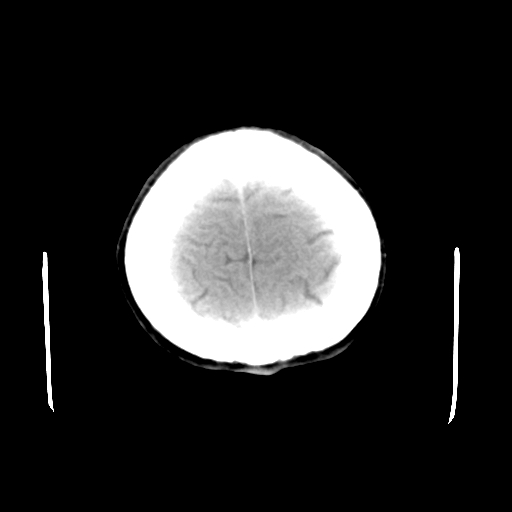

头颅ct平扫未见异常

未见明显异常!

颅脑ct平扫未见异常,必要时复查

未见明显外伤性改变。